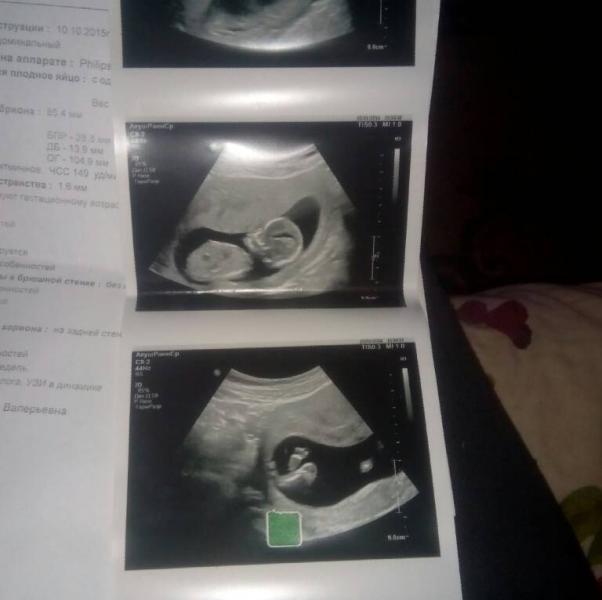

нам 14 недель..

ножки накрест..